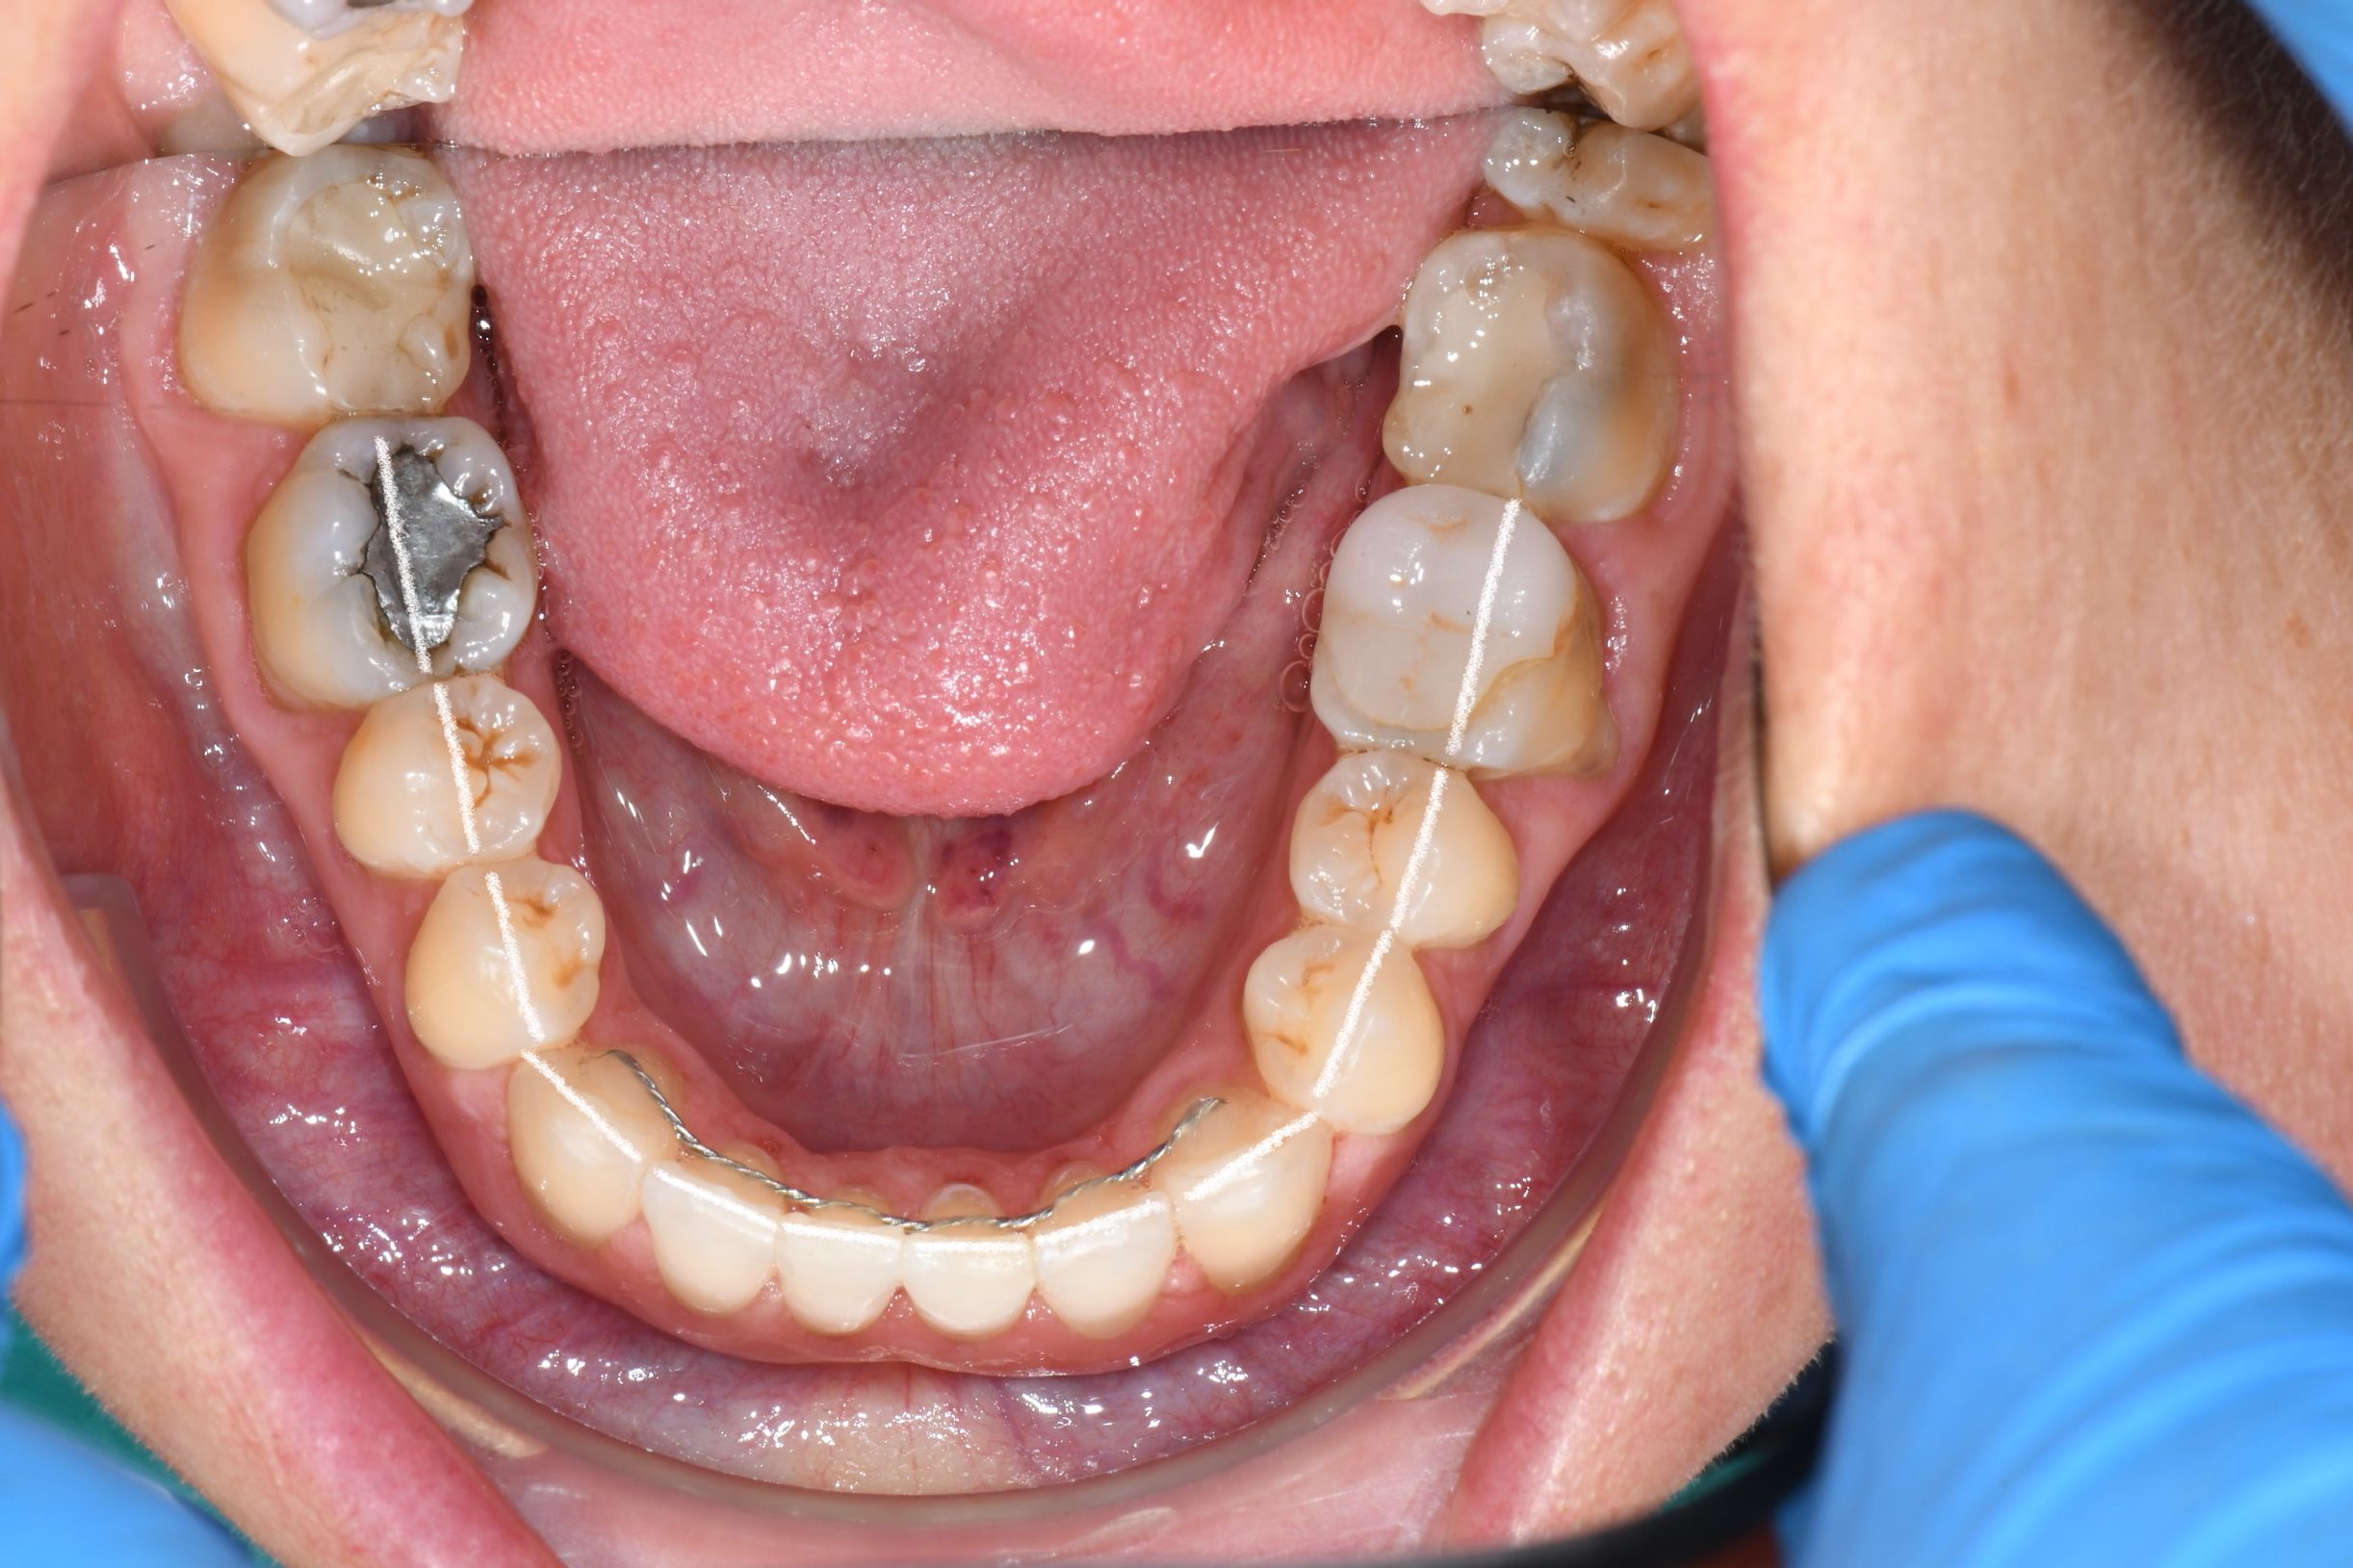

Az elmúlt évekből rengeteg szakmai referenciát tudnánk bemutatni, amelyek különböző fogszabályozási problémákat oldottak meg. Válogatva a több száz esetből, ezen az oldalon olyan képeket, információkat igyekeztünk bemutatni, amelyeknek a segítségével a jövőbeni pácienseinknek azt tudjuk üzenni: A Te fogsorod is lehet gyönyörű!

(Képeket a Pácienseink külön írásos beleegyezésével mutatjuk be!)